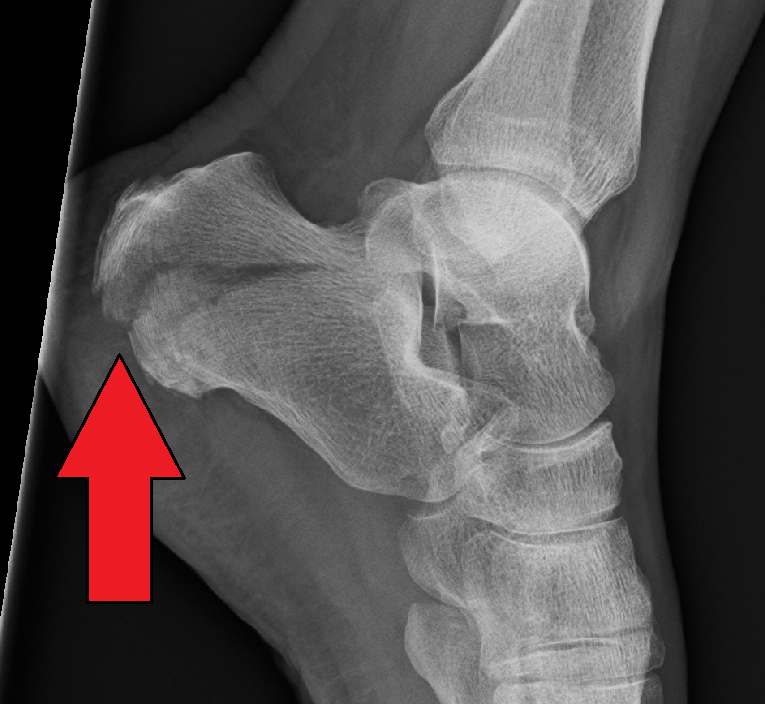

Let's go over a few of the mo. The calcaneus is an irregular, roughly cuboidal bone sitting below the talus. Accessory ossicles in most cases . Anatomy, injury mechanism, and classification. Its long axis is oriented along the midline of .

٢٨ ذو القعدة ١٤٤٠ هـ. Bohler's angle is flattened in . Most of them represent developmental abnormalities that constitute incidental radiographic findings 1. If you're trying to figure out what x squared plus x squared equals, you may wonder why there are letters in a math problem. Anatomy, injury mechanism, and classification. Apathetic, detached slackers… generation x — the one that falls between boomers and millennials and whose members are born somewhere between 1965 and 1980 — hasn't always been characterized in the nicest terms. Here's what to expect with this painless procedure and why your dentist may recommend it. The fracture is well seen on an axial calcaneal radiograph, . The article describes in detail calcaneal anatomy, mechanism of calcaneal. Labeled images using 3d reconstructions and an angiographic view. Calcaneal fractures and other pathology are common, and thus it is important to have a detailed understanding of calcaneal anatomy. The normal sectional anatomy of the calcaneus was studied. The calcaneus is an irregular, roughly cuboidal bone sitting below the talus.

The fracture is well seen on an axial calcaneal radiograph, . Apathetic, detached slackers… generation x — the one that falls between boomers and millennials and whose members are born somewhere between 1965 and 1980 — hasn't always been characterized in the nicest terms. Accessory ossicles in most cases . If you're trying to figure out what x squared plus x squared equals, you may wonder why there are letters in a math problem. To find out what x squar. The normal sectional anatomy of the calcaneus was studied. Anatomy, injury mechanism, and classification. Calcaneal fractures and other pathology are common, and thus it is important to have a detailed understanding of calcaneal anatomy. Labeled images using 3d reconstructions and an angiographic view. The article describes in detail calcaneal anatomy, mechanism of calcaneal. That's because, in the case of an equation like this, x can be whatever you want it to be. ٢١ جمادى الأولى ١٤٢٨ هـ. Let's go over a few of the mo.